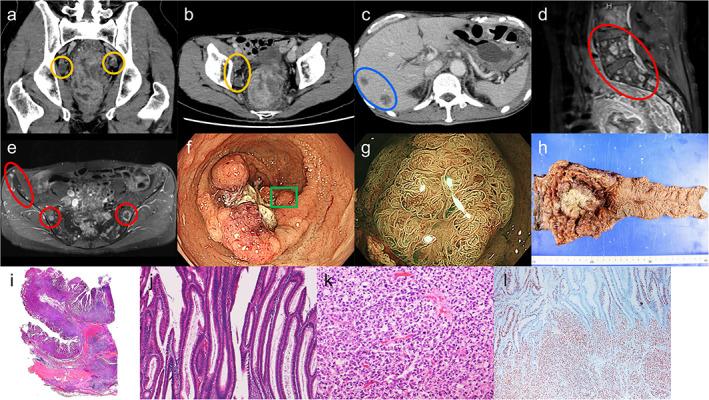

McKittrick-Wheelock syndrome (MWS) is a rare entity that has been described as electrolyte and fluid depletion secondary to secretory diarrhea caused by a large villous tumor in the colon or rectum. Most tumors associated with MWS are large but benign villous adenomas. Advanced cancers are seldom reported. We report a rare case of advanced rectal cancer with multiple liver and bone metastases presenting with MWS. A 59-year-old man was admitted to our hospital with a more than 3-year history of chronic mucous diarrhea. Laboratory data revealed hyponatremia, hypokalemia, hypochloremia, and renal failure. Based on the findings on colonoscopy, computed tomography, and magnetic resonance imaging, he was diagnosed with advanced rectal cancer with liver and bone metastases, and MWS. Following intravenous fluid treatment, abdominoperineal resection of the rectum with lymph node dissection was performed. The surgically resected specimen was a circumferential villous tumor measuring 110 × 80 mm. Histological examination of the resected specimens revealed signet ring cell carcinoma with villous adenoma and metastasis in regional lymph nodes. The renal dysfunction and electrolyte abnormalities that were present before surgery improved. Two courses of capecitabine were administered as adjuvant chemotherapy after the surgery. However, approximately 2 months after surgery, he died of poor general condition due to progression of the liver metastases.

摘要